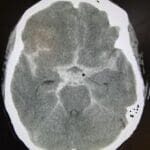

SAH

SAH patient intubated

SAH patient not intubated